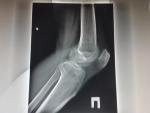

Снимки июля 2017г.

Еще снимок

На правом к.с. после разных обследований сделали артроскопию в конце ноября 2016г. Ситуация такая, что человек с начала марта 2017г. практически не может ходить (быстрое прогрессирование заболевания, в начале августа первые боли - затем через 2-3 недели , неустойчивость в коленях и только в эластичных наколенниках ходьба, в середине октября -только с тростью ходьба и далее ухудшение (с августа без нагрузок, с октября -больничный).С января 2017г. -полужеский Артез и трость. В январе 2017г. по КТ пятнистый остеопороз. С начала заболевания делали по три раза Ренген.снимки, МРТ, что за заболевание такое?